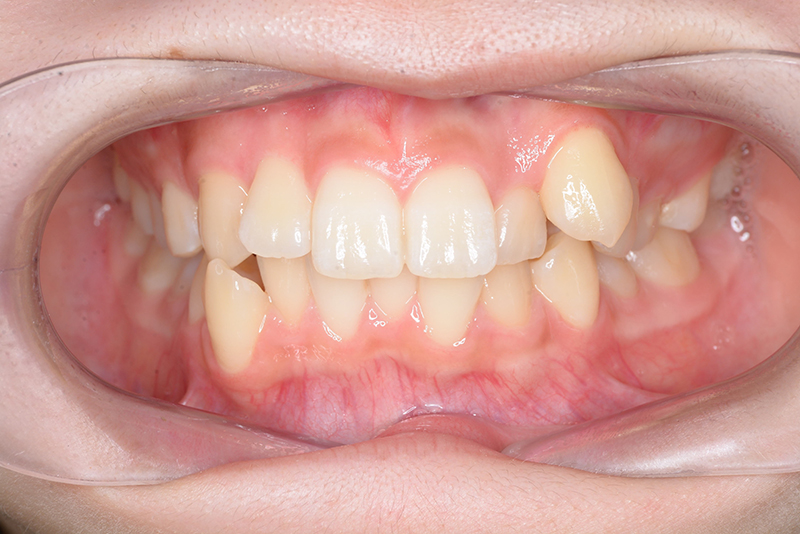

| 口腔内所見 | over jet 3.8mm、over bite 30mm、臼歯関係I級、上下顎前歯部に叢生が認められ、下顎正中は右側へ4.5mm偏位していた。左上5はCRの治療痕が認められた。 |

| 主訴 | 前歯のでこぼこ | 診断名 | アングルⅠ級叢生症例 | ||||

| 初診時年齢 | 15歳6ヵ月 | 性別 | 女 | 動的治療期間 | 23ヵ月 | ||